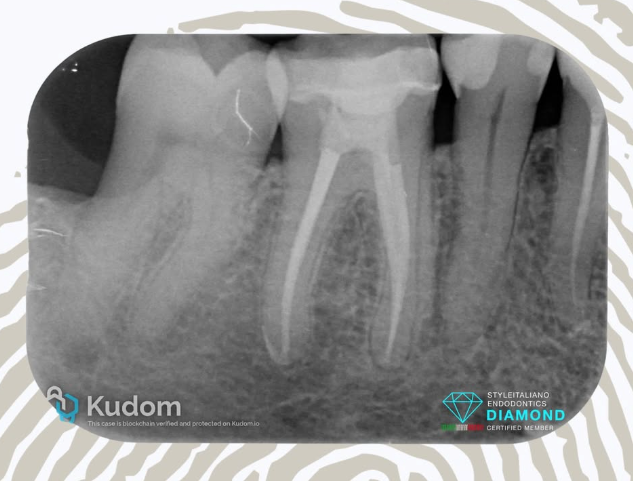

4.6: SINGLE VISIT RETREATMENT - L.E.O - 7 YEARS RECALL

A large periapical lesion was present on the mesial root of tooth 4.6, which had been previously treated many years ago and restored with a fiber post and crown.

The patient requested that the retreatment be performed through the crown, despite being informed that this was not the ideal approach.

After removal of the fiber post using an ultrasonic tip, the tooth was desobturated with rotary files, then shaped, thoroughly cleaned, and obturated in the same session.

CeraSeal bioceramic sealer was used with the Cold Hydraulic Condensation (CHC) technique, as the tooth was asymptomatic and no exudate was present in the canal.

The 1-year recall showed the not yet completed healing of the lesion and a fracture of the crown.

At the 7-year recall, complete healing of the large lesion was observed — it’s all about the outcome.

ARE BIOCERAMIC SEALER AND CHC RELIABLE? IT’S ALL ABOUT OUTCOME, NO FOLLOW UP NO ENDO.